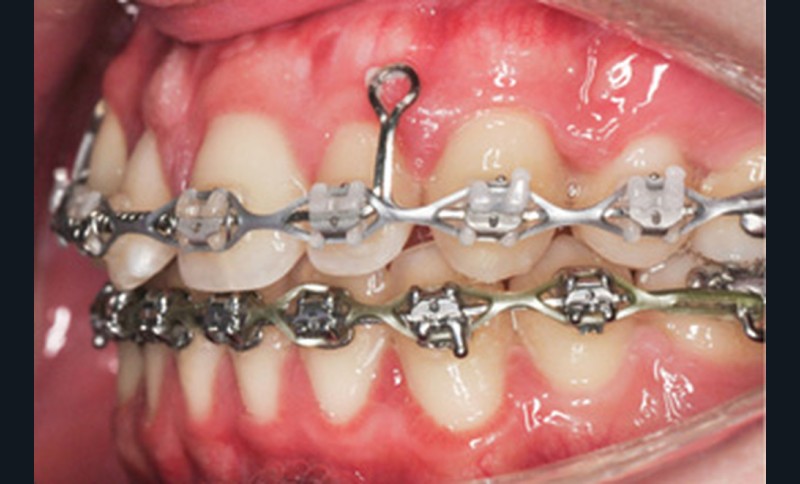

Le nivellement a nécessité trois arcs en Copper-NiTi (.014/.016 x .022/.019 x .025). Les mécaniques intra arcades (fermeture des espaces) et interarcades (élastiques de tractions intermaxillaires de classe II) ont été effectuées sur des arcs en acier .019 x .025. La gestion asymétrique de la mécanique de rétraction maxillaire a débuté par le recul de 23 (ancrage postérieur dentaire + élastiques intermaxillaires de classe II). Une fois 23 symétrisée avec 14 (substituant la 13), le centrage de 12 a débuté pour le remplacement de la 11. La rétraction du groupe antérieur par un arc à boucles de rétraction en acier .019 x .025 permet d’ajuster le torque radiculo-palatin pour contrer le rabbiting antérieur (fig. 2a-c).